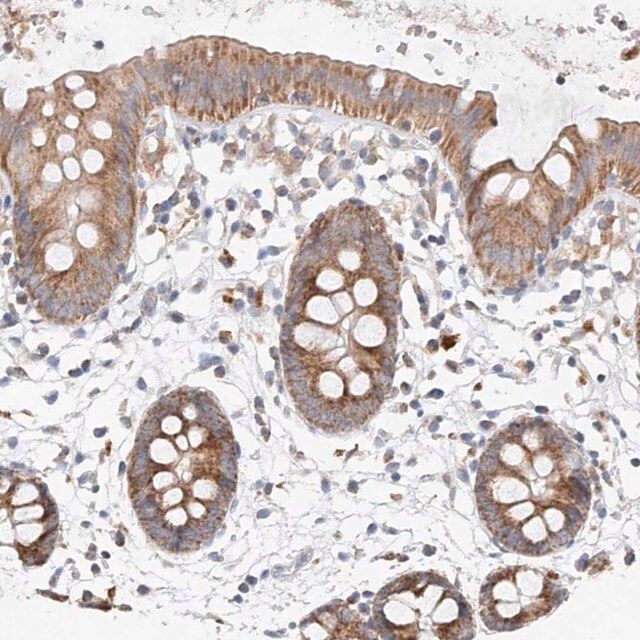

mitochondrial ribosomal protein L24 recombinant protein epitope signature tag (PrEST)

- IHC tissue array of 44 normal human tissues and 20 of the most common cancer type tissues.

| technique(s) | immunohistochemistry: 1:50-1:200 western blot: 0.04-0.4 μg/mL |